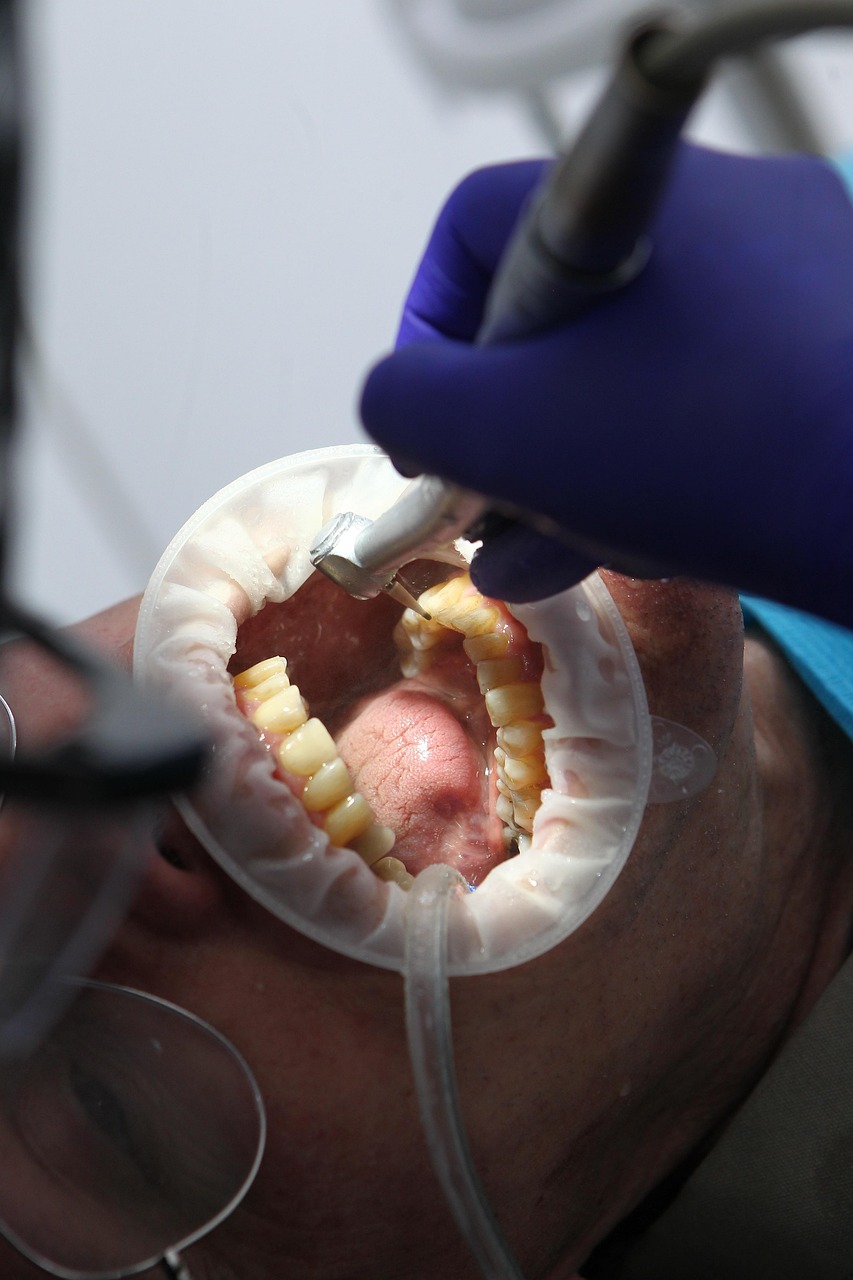

Keep your smile clean and healthy with professional dental scaling for plaque and tartar removal.